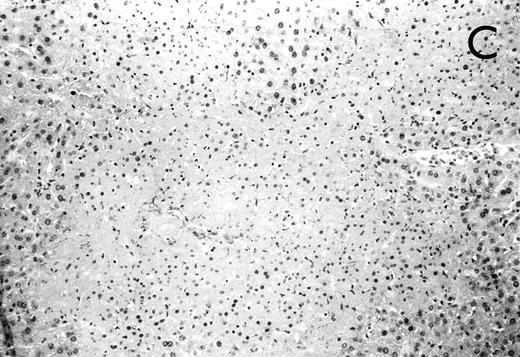

Histology further supported this observation. Control animals showed well-developed pneumonia with abscess formation (Fig3A) in their lungs, but in their livers, only small areas of inflammation with scattered microabscesses and foci of hepatic necrosis were observed (Fig 3B). In contrast, mice pretreated with G-CSF had only mild peribronchitic alterations in their lungs without signs of containment of inflammation such as abscess formation (Fig 4A). Livers and spleens of mice pretreated with G-CSF were severely altered, showing large abscesses which contained massive amounts of bacteria (Fig 4B). In addition, large necrotic areas surrounded by granulocytes were observed in the livers (Fig 4C). When MoAb III/5-1 was administered in addition to pretreatment with G-CSF, almost all changes observed in animals pretreated with G-CSF were reversed: there were only minor bronchial and peribronchial infiltrations by granulocytes (minimal change focal pneumonia), and the livers showed small microabscesses as observed in control mice. When treatment with G-CSF was started at 24 hours after bacterial challenge, a mixed pattern was observed. In the lungs, there was a beginning pneumonic reaction and a moderate perivascular and septal edema. However, in the liver there was almost no difference to the severe alterations observed in mice pretreated with G-CSF: huge abscesses loaded with bacteria joined extended necrotic areas.

(A) Micrograph of lung tissue 48 hours after intranasal infection with 1 × 103 CFU of K pneumoniae B5055 and pretreatment with G-CSF (50 μg/kg sc) at −48 hours, −36 hours, −24 hours, and −12 hours before infection. Peribronchiolar neutrophils without destruction of lung parenchyma. H&E; original magnification ×150. (B) Splenic abscesses in the red pulp containing numerous gram-negative bacilli are found. H&E; original magnification ×370. (C) Confluent hepatic necroses. H&E; original magnification ×150.